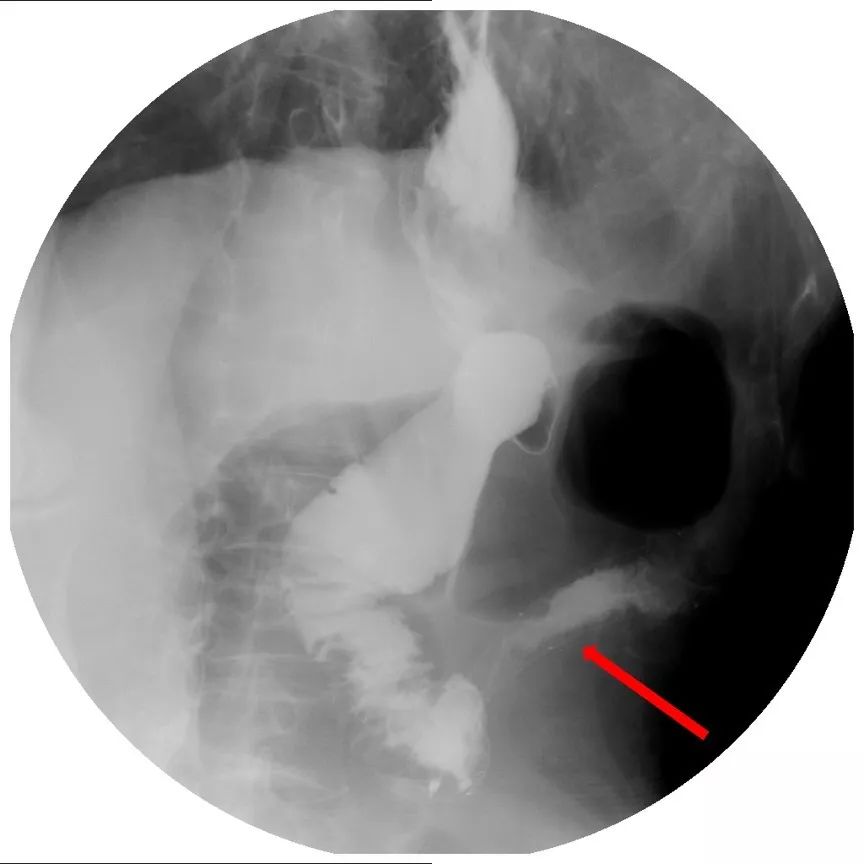

到此为止,患者已经接受了3次大的腹部手术,并接受了放化疗。但是,疾病仍然进展。2018年6月下旬患者出现恶心、呕吐,腹痛、腹胀,不能进食,X线腹部平片及腹部CT检查提示肠梗阻合并感染(见图1、图2),给予抗炎对症治疗效果差。结肠镜检查见横结肠占位伴梗阻(图3)。患者腹痛腹胀进行性加重,出现高热、血压下降等感染性休克症状。患者已经无法耐受再次开腹手术!

图2 腹部CT可见扩张的肠管和气液平